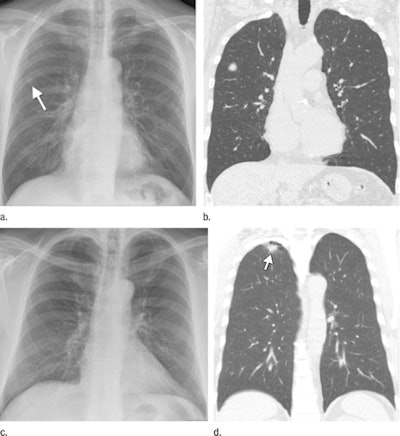

| (a) Digital radiography can localize lung cancers, such as an 11.4-mm diameter malignancy considered as definitely present in separate readings by three radiologists and a radiology resident. (b) Tumor's presence is confirmed with CT. (c, d) But lung malignancies can be undetectable with DR, even when their presence on CT had been previously disclosed to the observers. Images provided by Dr. Bartjan de Hoop; republished with permission of the Radiological Society of North America. |

Twenty-four (44%) malignancies were correctly localized by the four physicians. At level 5, for example, the sensitivity of DR for correctly localized malignant lesions ranged from 18% to 49% at a specificity of 100%. The false-positive rates in the control group ranged from 0% to 13%.

Seven (13%) metastatic lesions were missed by all observers, and three of the seven remained undetectable on the radiographs even when CT findings were known. Depending on reader experience, de Hoop and colleagues concluded that 22% to 63% of the lung cancers detected with CT would have been missed if chest DR had been used alone.

Still, the researchers found that DR can equal the 94% lung cancer detection rate achieved with CT screening, but this high level of performance requires an experienced or well-trained reader and must be delivered at the expense of a high false-positive rate.